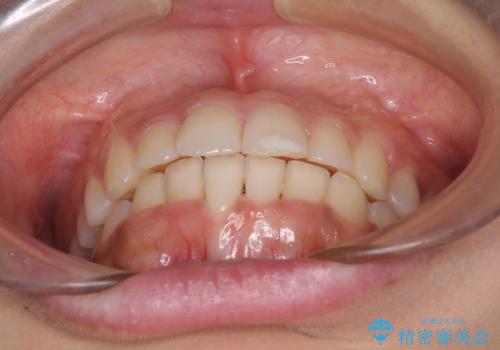

大きなトラブルもなく、順調に歯列が整ったため、僅か9ヶ月で装置を外すことができました。

あまりに短期間であったため、患者様自身も非常に驚いていらっしゃいました。